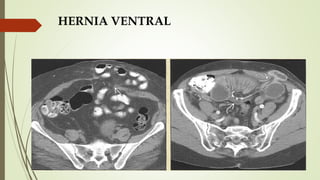

HERNIA VENTRAL

 La mayoría aparecen en la línea media a través de las

aponeurosis que forman la línea alba 18-22% de los pacientes

tienen hernias múltiples.

 Los factores que i la probabilidad de que aparezca una hernia

incluyen obesidad, diabetes, esteroides, enfermedad

pulmonar.

 TC + C: considerar hacer que el paciente haga una maniobra

de Valsalva durante el estudio.